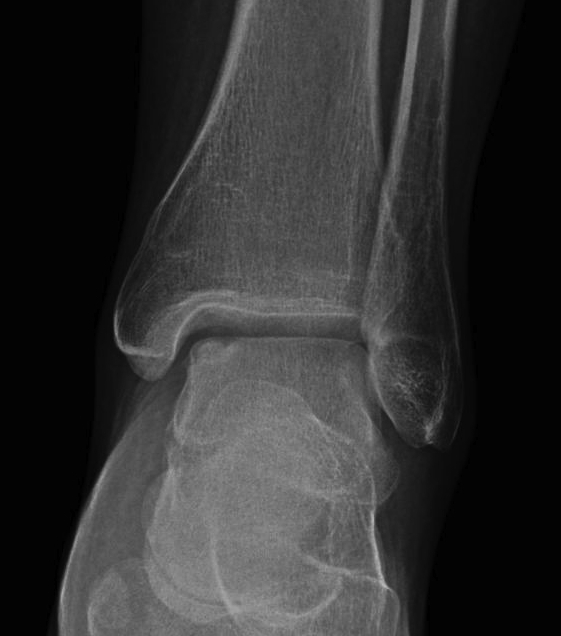

Xray

Stage II medial osteochondral fragments

Stage III medial osteochondral fragments

Stage IV anterolateral osteochondral fragment